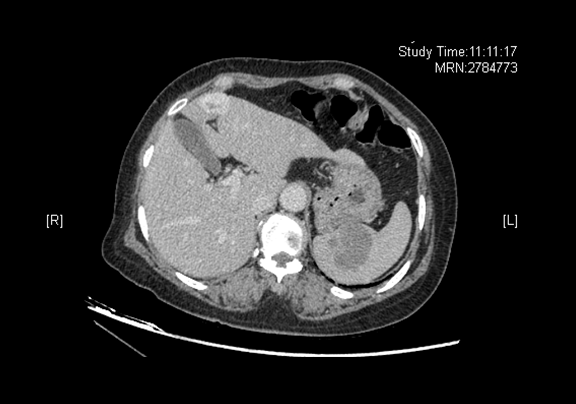

术前CT检查:

静脉期

全腹CT 肝左叶内略低密度灶,脾脏内略低密度灶

将0.625mm双源薄层CT资料的静脉期和动脉期Dicom格式文件导入海信CAS系统。

通过调节窗宽窗位调整CT序号,对肿瘤,肝实质,胆囊,下腔静脉,肿瘤,肝动脉、门静脉及肝静脉等进行三维重建;系统自动计算肿瘤体积和肝脏体积。